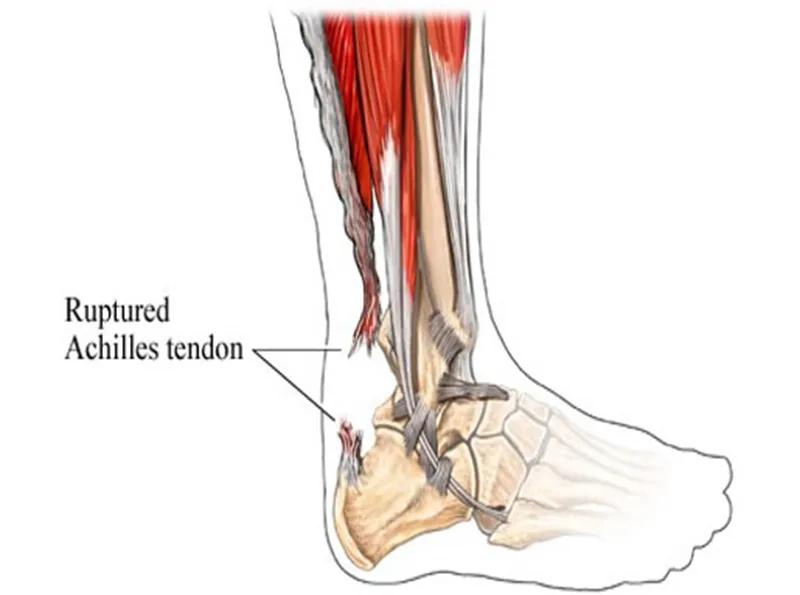

跟腱是人体最长、最强壮的肌腱,起于腓肠肌和比目鱼肌,止于跟骨结节,长约15cm。它在腱的背侧约有4-8层润滑层,位于深筋膜与腱组织之间,每层有独自的营养血管。具有踝关节跖屈,完成脚尖站立、正常走路、跑、跳、上下楼梯等动作的功能。

跟腱断裂容易发生于偶尔参加运动的中年人,所以也称这类人为“周末运动员”。踝在过伸位突然用力,断裂多发生在跟腱止点上方2~6cm,因为跟腱自上而下逐渐变窄增厚,跟骨结节上方2~6cm处最窄,此处最薄弱。

肌腱断裂可能是由于血管相对稀少及反复微小创伤综合所致,由于血管分布减少,反复微小创伤引起的炎性修复过程跟不上应力作用,此时再承受机械超负荷便会使其完全断裂。跟腱断裂的危险因素如下: